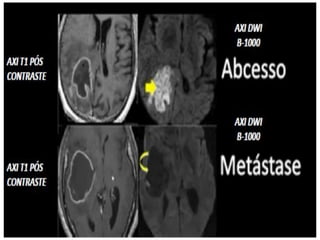

PÓS-CONTRASTE EM T1

DIFUSÃO (DWI)

• Estudo do movimento

browniano.

• Restrições de fluxo arterial.

• Utilizado pra casos de AVC e

AIT.